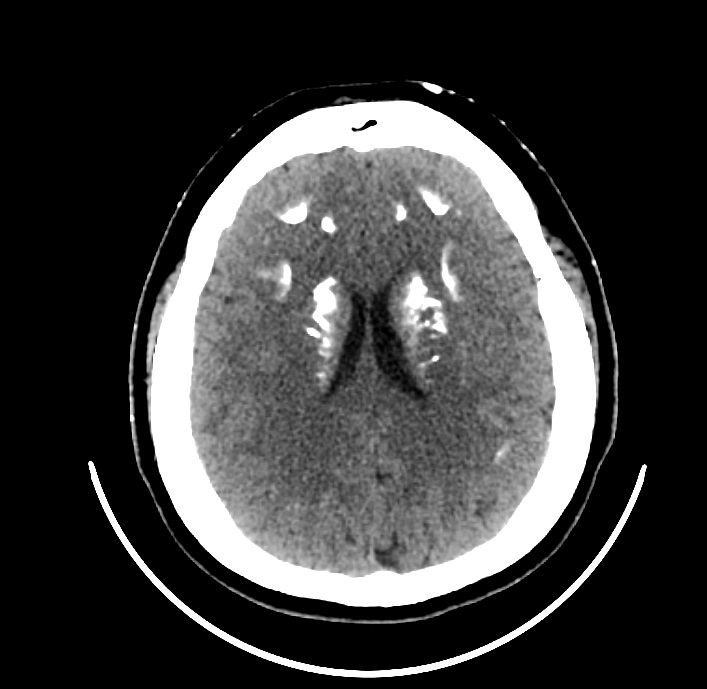

В ФГБУ НМИЦ эндокринологии наблюдается женщина 35 лет с ожирением, низкорослостью, депрессивными расстройствами, нарушениями кальций-фосфорного обмена, гипотиреозом. С 3 лет у пациентки отмечались тонические судороги на фоне фебрильной лихорадки и периодические миалгии. Впервые обследование проведено в 12 лет в связи с появлением карпопедальных спазмов, когда была выявлена гипокальциемия (Са общ. 1,3, при норме 2,0–2,6 ммоль/л), гиперфосфатемия (2,66 ммоль/л при норме 0,7–1,6) на фоне повышенного уровня ПТГ (268 пг/мл). Во время обследования в стационаре также впервые обратили внимание на особенности фенотипа: у девочки отмечалось ожирение, укорочение IV и V пястных и плюсневых костей (рис. 1, 2), пальпировались плотные подкожные образования, не спаянные с окружающей тканью, безболезненные. Гистологическое исследование биоптата образований доказало наличие подкожных кальцификатов с распространением в перимизий. По данным мультиспиральной компьютерной томографии (МСКТ) головы выявлено обызвествление базальных ядер и субкортикальных отделов головного мозга (рис. 3). Был установлен диагноз «псевдогипопаратиреоз Iа типа». Молекулярно-генетическое исследование подтвердило наличие мутации в гене GNAS – гетерозиготная мутация GNAS в сайте сплайсинга с.585+2Т>С. По поводу резистентности к ПТГ назначен альфакальцидол, в последующем к терапии были добавлены препараты кальция. Прием препаратов осуществлялся под контролем показателей кальция крови с периодической коррекцией дозы. В 20 лет впервые выявлен субклинический гипотиреоз и назначена заместительная терапия препаратом левотироксина натрия с дальнейшей коррекцией дозы в зависимости от уровня ТТГ при контроле в динамике. Клинических признаков гипогонадизма не отмечалось: менархе в 12 лет, менструальный цикл регулярный. При сборе семейного анамнеза не было выявлено особенностей, указывающих на возможность наличия у родственников НОО или гипокальциемии: родители нормального роста, брахидактилии, подкожных образований у них не имеется, судорожных эпизодов или криптогенной эпилепсии ни у родителей, ни у ближайших родственников не отмечалось. У пациентки нет детей, но было 4 беременности, все окончившиеся абортами. Одна беременность – замершая, один аборт по желанию пациентки, 2 последние беременности были прерваны после получения результатов пренатальной диагностики, доказавшей наличие у плода той же мутации в гене GNAS, что и у матери.

Рис. 3. Отложение кальцинатов в базальных ганглиях и субкортикальных отделах.

На момент диагностики заболевания в 12 лет уже имелось обызвествление базальных ядер и субкортикальных отделов головного мозга, отражающих наличие синдрома Фара. Синдром Фара является неспецифическим осложнением длительной гиперфосфатемии и гипокальциемии, ведущих к отложению солей кальция в тканях головного мозга и хрусталике. Считается, что отложение кальцинатов в структурах головного мозга приводит к развитию нейропсихических нарушений в виде снижения памяти, концентрации внимания и нарушений экстрапирамидной системы в виде дистонии и расстройств непроизвольных движений, что обосновано характером локализации кальцинатов. В статьях, посвященных редким вариантам психических нарушений, у пациентов с ПГП основой психических расстройств называют именно синдром Фара. Тем не менее нельзя считать синдром Фара ведущей причиной психических нарушений: одним из характерных признаков НОО является умственная отсталость, манифестирующая, как правило, с первых лет жизни, ее развитие обусловлено влиянием нарушенного внутриклеточного сигналинга и сниженной активностью Gas и наблюдается вне зависимости от синдрома Фара. Кроме того, наличие синдрома Фара не обязательно будет иметь клинические проявления. Несмотря на длительное существование кальцинатов в экстрапирамидных структурах, у нашей пациентки не было выявлено характерных неврологических нарушений, а имеющаяся депрессия могла быть не столько проявлением синдрома Фара, сколько компонентом НОО, отражающим нарушение активности Gas, либо мог иметься экзогенный компонент: сама пациентка связывала свое тяжелое психоэмоциональное состояние со стрессом после перенесенного последнего аборта.